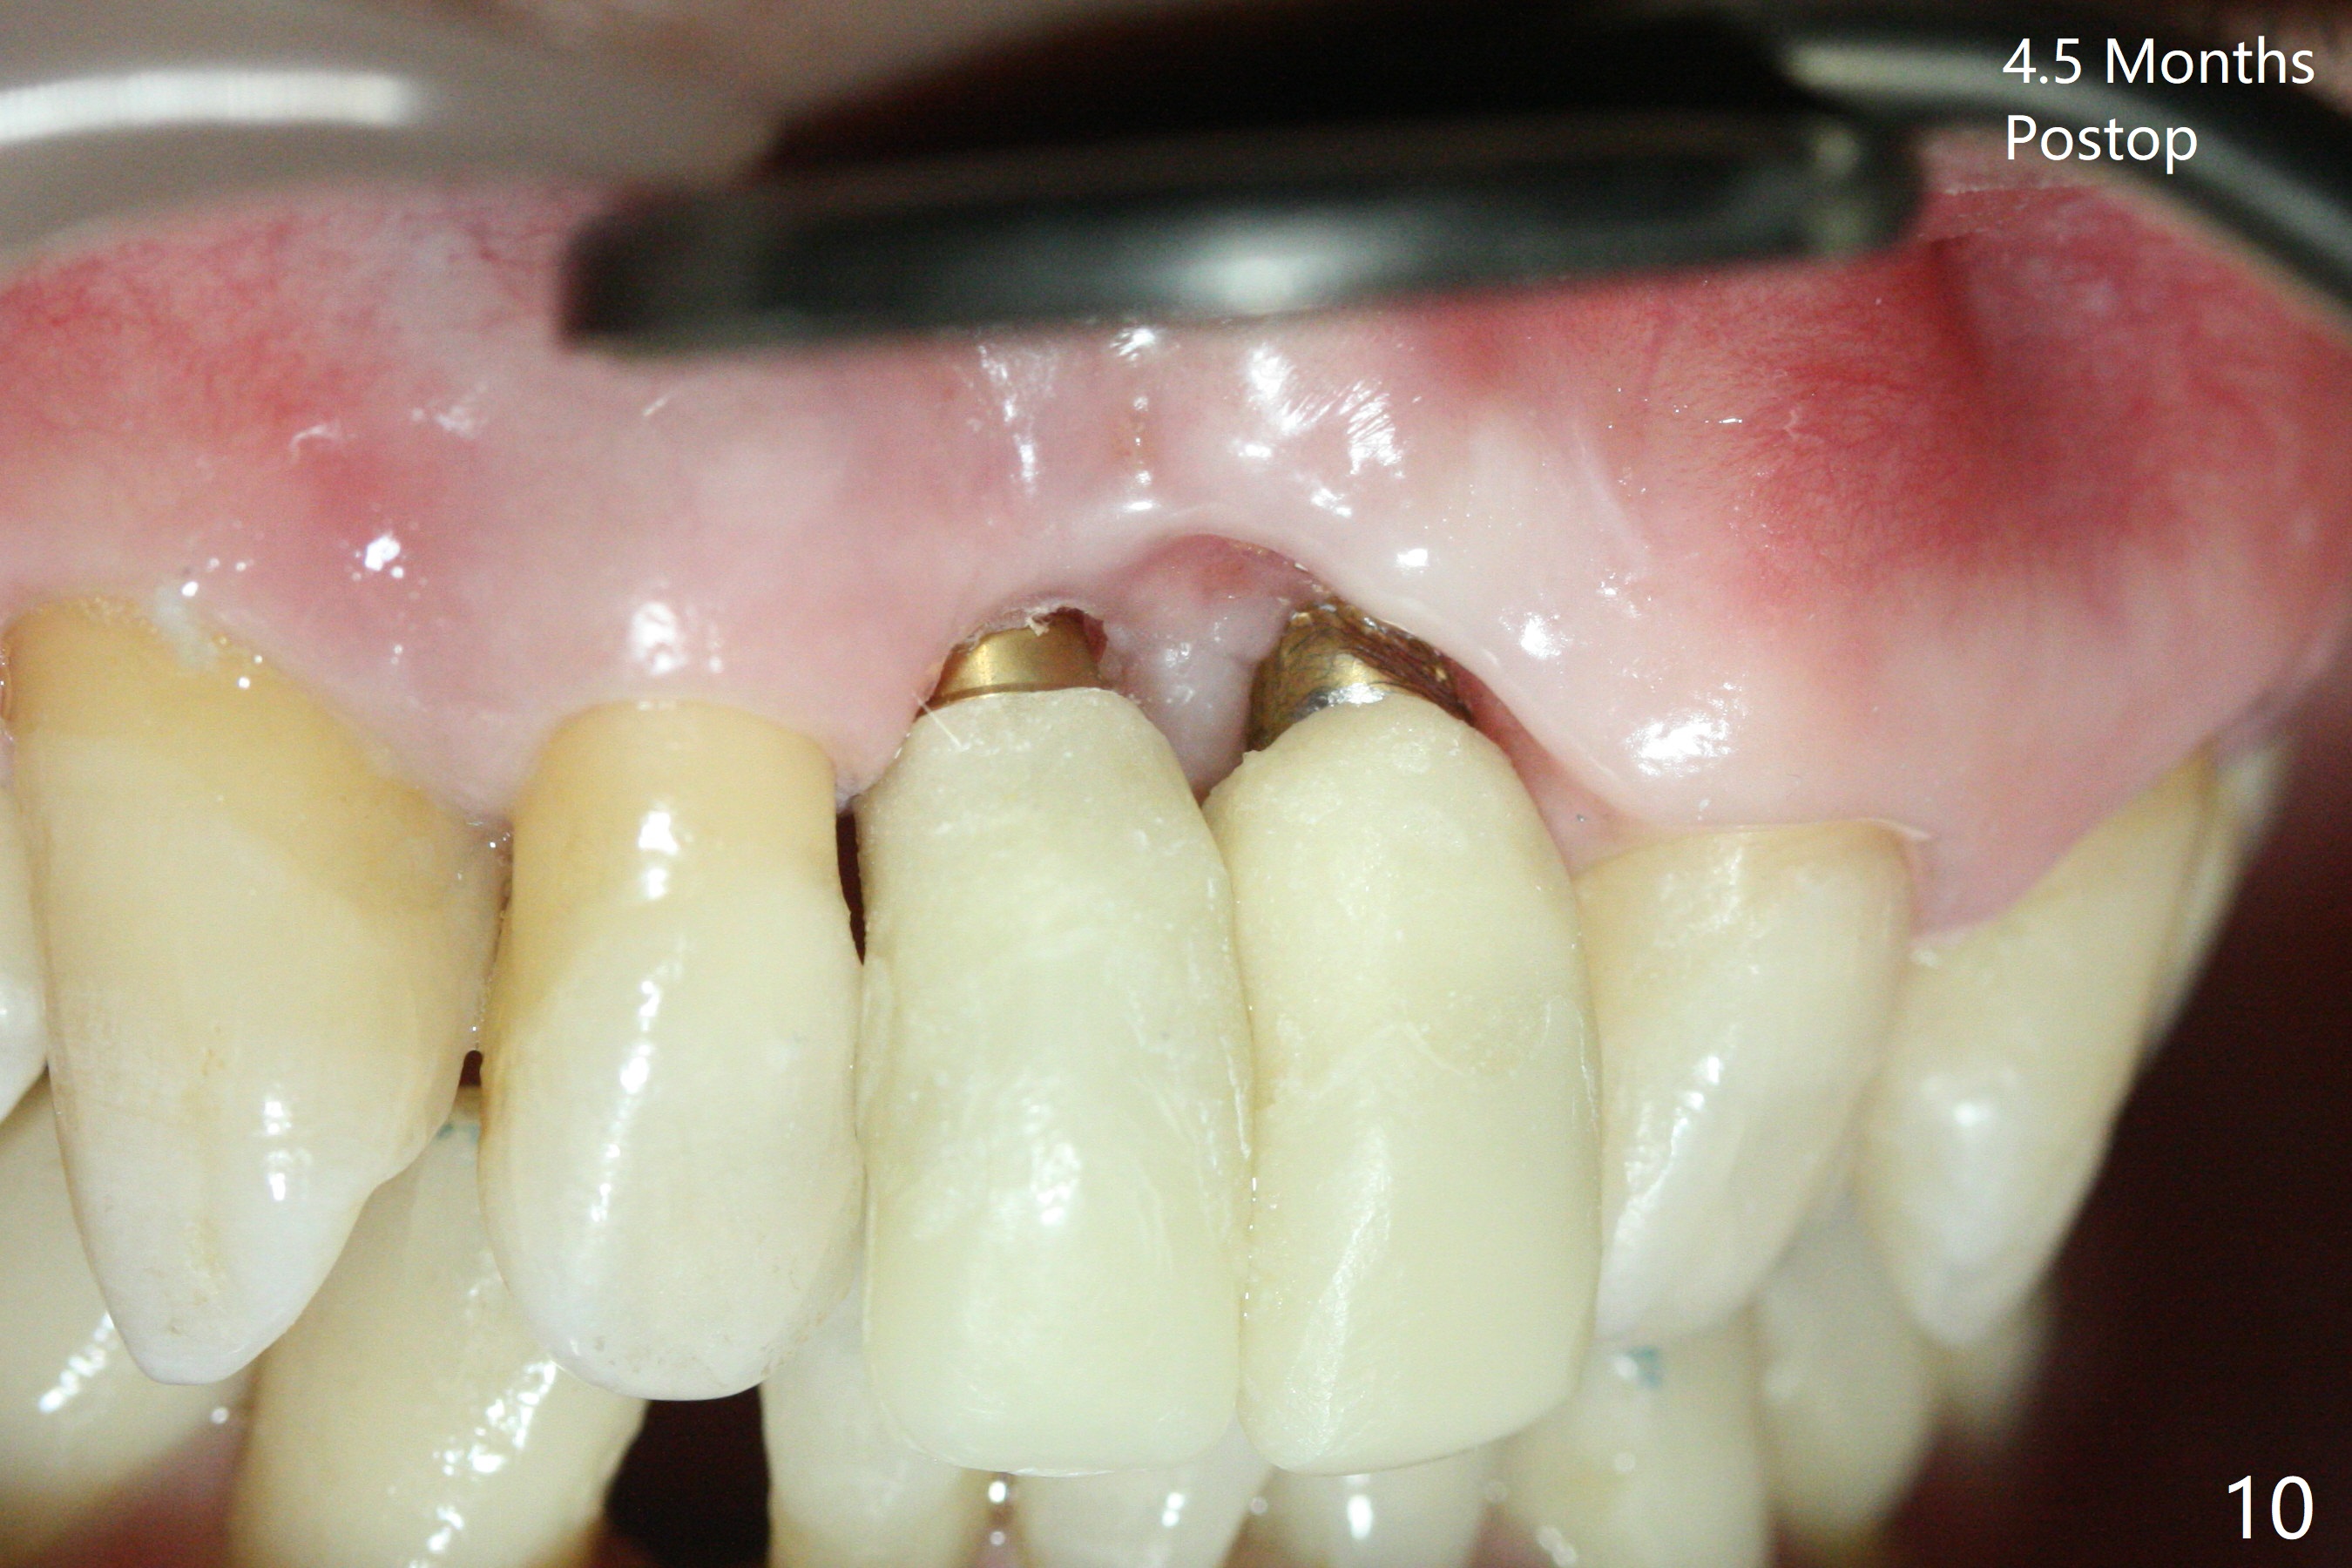

There is no buccal plate at #8 or 9 when the teeth are extracted as well as severe soft tissue defect at #8. Osteotomy is initiated as palatal as possible (Fig.1). When 3.5x13 mm implants are placed initially, the one at #8 is supracrestal (Fig.2 ^). To reduce the chance of peri-implantitis, the implant is placed deeper (Fig.3 (~2 mm implant threads exposed buccally)) with placement of sticky bone around the implants and 4.5x5.5(4) mm abutments (Fig.3 *). The buccal soft tissue defect #8 is repaired with a piece of PRF membrane (Fig.4 *), followed by periodontal dressing. Smaller 2-piece implants (3 mm, IBS) with smaller abutments (4 mm) may further reduce chance of periimplantitis and easy buccopalatal reduction of the abutments for restoration. The periodontal dressing remains stable 7 days postop (Fig.5) because it wraps around the abutments (Fig.6 A). By the time the periodontal dressing gets loose, #8 buccal soft tissue defect should be healing. When breaking-down periodontal dressing is removed 17 days postop, the coronal abutments and bone graft are exposed; after fabrication of provisional crowns (Fig.7), periodontal dressing is re-applied buccally. When the second dressing dislodges 5 weeks postop, the buccal soft tissue appears to reduce (Fig.8). Raising flaps may be less traumatic. A piece of bone graft is being extruded 4 months postop (Fig.9 >). After the abutments change from 4.5x5.5(4) to 4.5x7(3) mm, new temporary crowns are fabricated (Fig.10 (4.5 months postop)). CT shows apparent buccal bone at #8 and 9 (Fig.11,12). How to improve cosmetic?